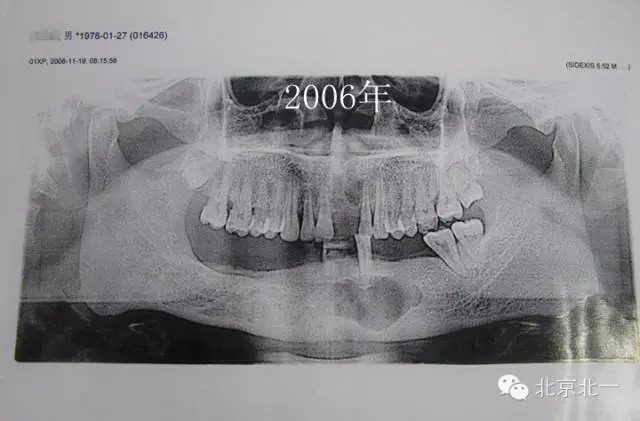

患者男,33歲,左下頜囊腫復(fù)發(fā)兩次就診。

圖一、初診時(shí)全景片